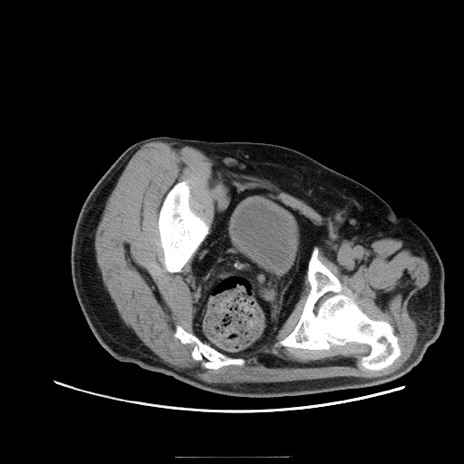

症例22(横断像)

【症例】50歳代男性

【主訴】腹痛

【現病歴】AVMからの被殻出血のため回復期リハ病棟入院中。 本日午後3時頃急に下腹部痛が出現した。

【既往歴】AVM、被殻出血、虫垂炎、高血圧

【身体所見】意識晴明、左半身不全麻痺、会話の理解は良好、36.5°C、腹部:膨隆、全体に板状硬、下腹部正中に圧痛点あり、反跳痛-、筋性防御不明、右下腹部にope scar

【データ】WBC 9400、CRP 0.06